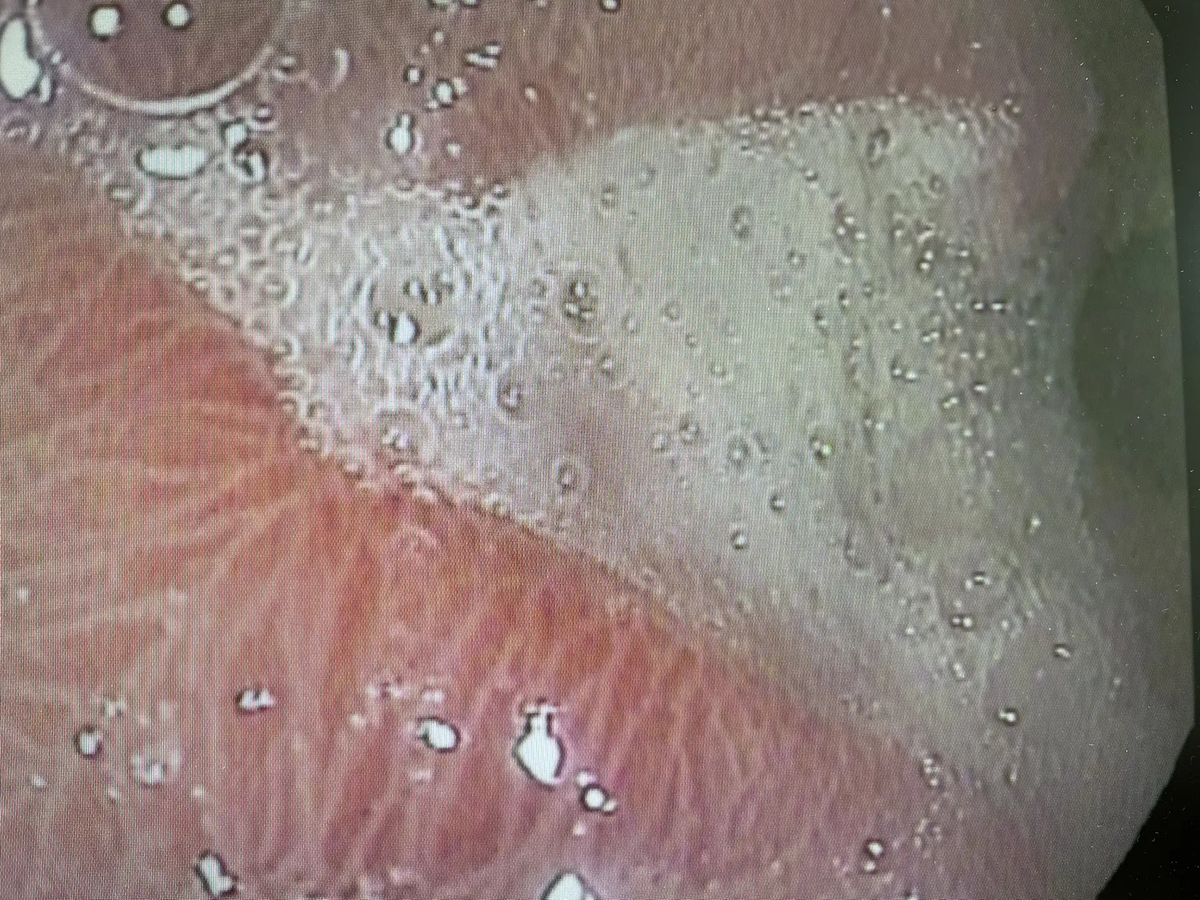

• Желудок: стенки отёчные, а в нижнем отделе (антральном) описывается картина «булыжной мостовой» и видны точечные эрозии — маленькие поверхностные повреждения. В желудке обнаружена желчь, хотя там её быть не должно. Это называется дуодено-гастральный рефлюкс.

Если перевести с медицинского на человеческий: в верхних отделах пищеварительной системы есть воспаление, которое затронуло всё — от пищевода до двенадцатиперстной кишки. Есть эрозии, требующие внимания, и есть заброс желчи, которая дополнительно раздражает стенки.